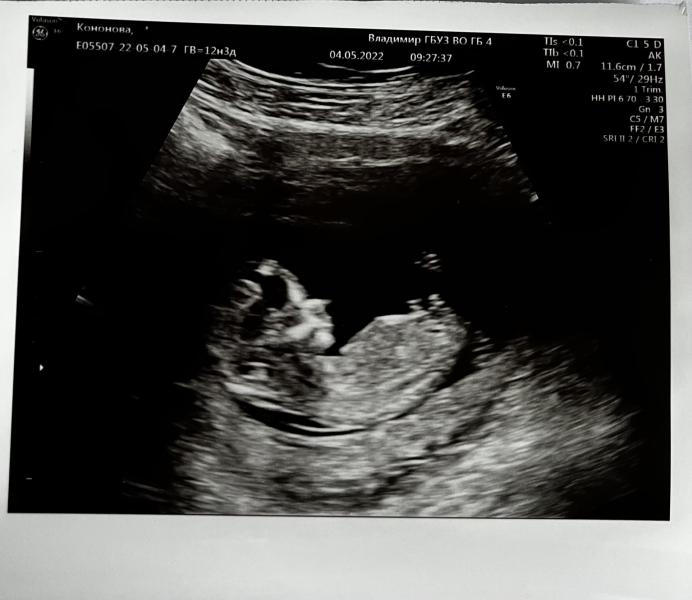

Первое плановое УЗИ: все хорошо, малыш растет! Ручки, ножки, носик - все на месте, ура!

Сегодня были на первом плановом узи!

Все показатели в норме, бусинка растёт. Ручки-ножки-носик торчат)

Ктр сколько?

66,2 мм :)

Старшая дочь с линейкой бегала, сравнивала сколько это)